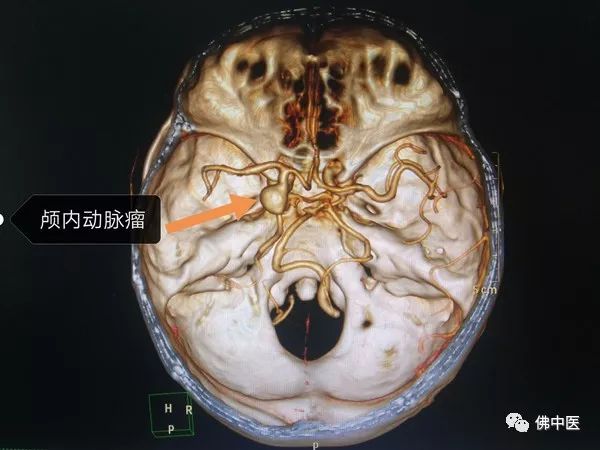

家住湖南的肖女士今年48岁,在无明显诱因下出现头痛头晕,伴恶心反酸的症状。肖女士警惕性很高,感觉“不对劲”后,立即在当地医院就诊。行头颅MRI+MRA发现左颈内动脉与左后交通动脉交界处有一大小约10mm﹡11mm动脉瘤。

经过多方打听,肖女士决定跨省前来我院神经外科贾若飞主任处求诊。贾若飞根据患者动脉瘤的大小、形态、位置、脑血流动力学状况、患者状态等因素,决定采用微创介入的治疗方式行动脉瘤栓塞术。

术中全麻成功后,于患者右侧股动脉穿刺,类似平时打点滴时穿刺一般,创伤极小,遂经过微导管、微导丝准确到达责任血管及载瘤动脉。由于患者后交通动脉血管迂曲,动脉瘤又位于颈内动脉分叉处,先通过支架辅助技术植入支架后,填入弹簧圈栓塞动脉瘤。手术顺利完成后,肖女士如释重负,频频称赞贾若飞团队妙手驱恶疾。

保留胚胎型大脑后动脉的动脉瘤介入栓塞术